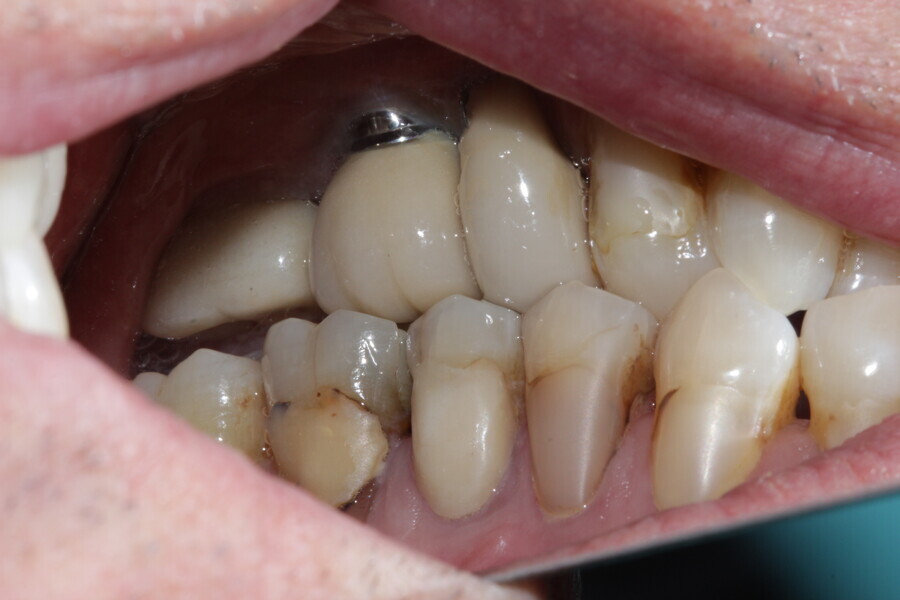

Figure 8 Right side in occlusion before treatment